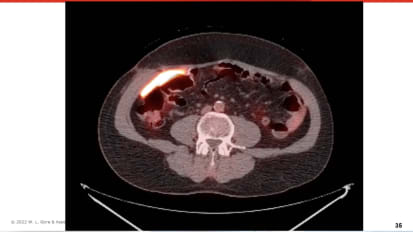

Matthew I. Goldblatt, M.D., FACS, discusses a case study of a patient undergoing treatment for simultaneous colon and rectal cancers and had a prior low anterior colon resection procedure with a diverting ileostomy.